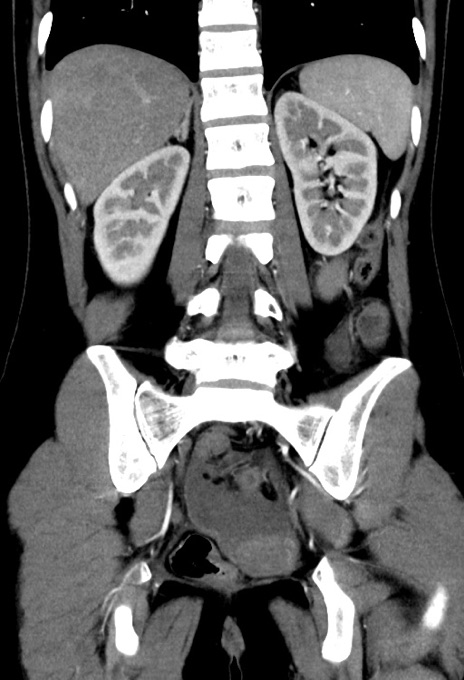

症例17(冠状断像)

【症例】20歳代女性

【主訴】嘔吐、下腹部痛

【現病歴】昨日夕食後に嘔吐し下腹部痛が出現。本日になっても嘔吐持続し改善しないため来院。

【身体所見】意識清明、BT 37.2℃、BP 108/67mmHg、腹部:平坦、やや硬、下腹部正中から右にかけて圧痛あり、反跳痛軽度あり、tapping pain(+)。

【データ】WBC 13600、CRP 14.94